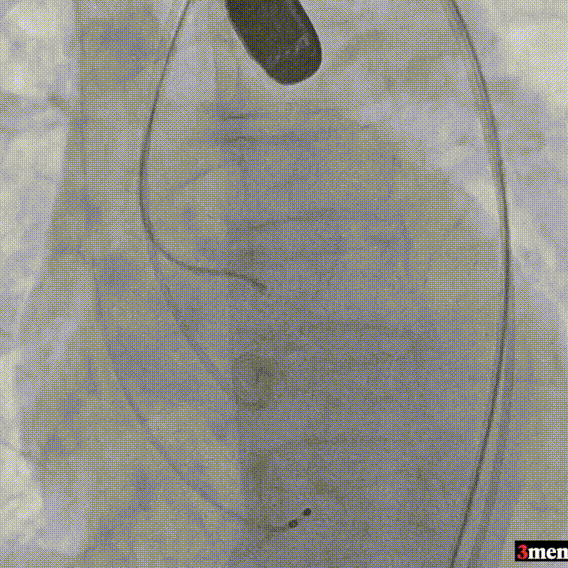

手术过程回顾:

患者全麻后,右侧股动脉建立主入路,主动脉根部造影显示主动脉瓣无明显钙化。心室内轻中量反流,主动脉及心脏情况整体较为稳定,根据术前策略预装23mm瓣膜。超硬置入左心室后,因超硬压迫无冠瓣叶导致急性反流,病人血压降至40mmHg,遂迅速将输送器送入主动脉根部,快速释放瓣膜后,病人血压恢复至正常。瓣膜脱钩后造影显示左冠开口存在一定狭窄,IVUS评估左冠开口狭窄约60%,符合PCI指征,植入开窗支架改善狭窄,最终再次造影加IVUS评估左冠开口,确定狭窄解除。

右侧股动脉穿刺

主动脉根部造影

直头导丝跨瓣

跨瓣压差测量

输送器定位

完全释放后造影疑似左冠狭窄

IVUS探查左冠开口狭窄60%

放置开窗支架

球囊后扩支架

假体瓣膜形态良好,无明显瓣周漏

术后测量跨瓣压差仅为1mmHg